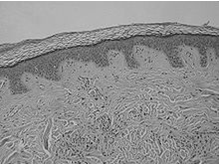

Строение кожи

Кожа в разрезе

Кожа состоит изэпидермиса,дермыи подкожно-жировой клетчатки (гиподермы).

- Эпидермисвключает в себя пять слоев эпидермальных клеток. Самый нижний слой —базальный — располагается набазальной мембранеи представляет собой 1 ряд призматического эпителия. Сразу над ним лежитшиповатыйслой (3-8 рядов клеток с цитоплазматическими выростами), затем следуетзернистыйслой (1-5 рядов уплощенных клеток),блестящий(2-4 ряда безъядерных клеток, различим на ладонях и стопах) ироговойслой, состоящий из многослойного ороговевающего эпителия. Эпидермис также содержитмеланин, который окрашивает кожу и вызывает эффект загара.

- Дерма, или собственно кожа, представляет собой соединительную ткань и состоит из 2-х слоев —сосочковогослоя, на котором располагаются многочисленные выросты, содержащие в себе петли капилляров и нервные окончания, исетчатогослоя, содержащего кровеносные и лимфатические сосуды, нервные окончания, фолликулы волос, железы, а также эластические, коллагеновые и гладкомышечные волокна, придающие коже прочность и эластичность.

- Подкожно-жировая клетчаткасостоит из пучковсоединительной тканиижировых скоплений, пронизанных кровеносными сосудами и нервными волокнами. Физиологическая функция жировой ткани заключается в накоплении и хранении питательных веществ. Кроме того, она служит для терморегуляции и дополнительной защиты половых органов.